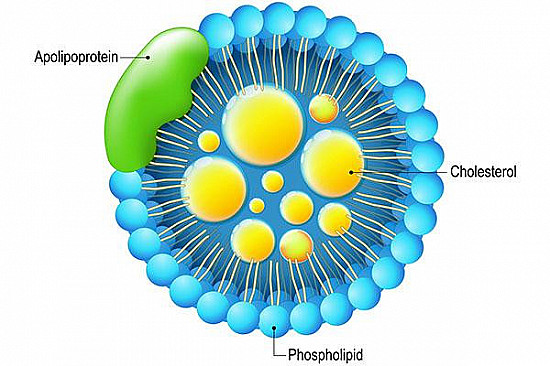

Is an apoB test a better way to check your cholesterol?

Is an apoB test a better way to check your cholesterol?